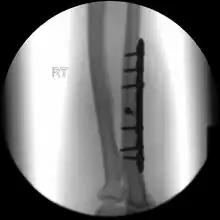

Treatment

When there is a displaced fracture or when the radioulnar joints are involved an operation is often performed, using either flexible rods or screws and plates in order to reduce the fracture and immobilise the bone.[3]